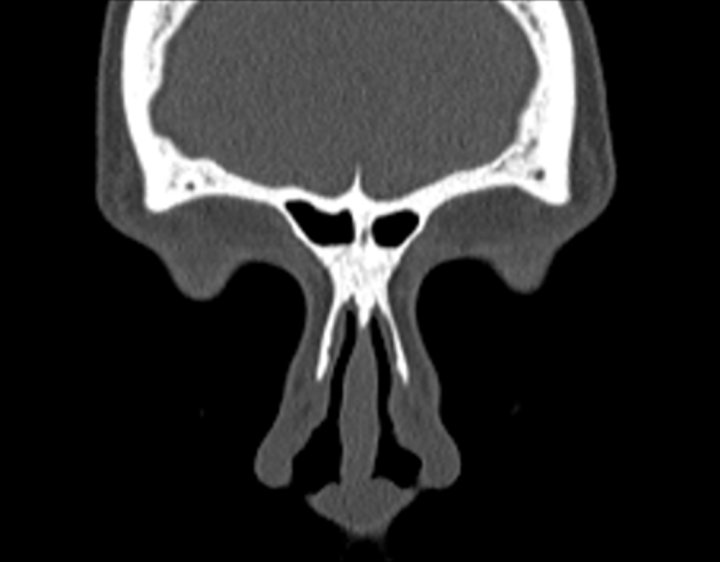

Click any image for labels.